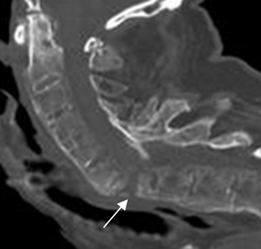

Fig 59 B. Lesiones Romanus.

A: RM sagital en T1 y B: RM sagital en T2. Lesión en la esquina posterior del cuerpo vertebral cervical, hipointenso en T1 e hiperintenso en T2, por lesión Romanus de evolución aguda.